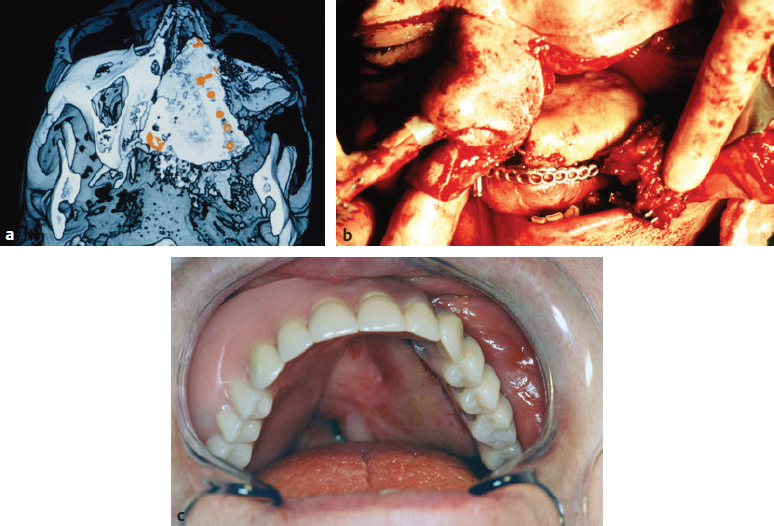

CHAPTER Modern plastic surgery concepts are based on the paradigm that plastic surgery must restore function as well as anatomy in all cases, regardless of the indication for surgery. In the case of facial plastic surgery, respecting the facial proportions is an elementary prerequisite for achieving an aesthetic reconstruction.1 The facial skeleton is a lightweight, mechanically stable structure that contains pneumatized cavities, houses organ systems, and allows for the fixation of the facial soft tissue envelope in a way that maintains musculoskeletal balance. In the case of loss or aplasia of facial parts, facial disfigurement increases in parallel with the extent of the maxillofacial defect. In this situation, ignoring the functional anatomy during the reconstruction effort invariably results in unsatisfactory outcomes. Since the introduction of microsurgical flap transfer, other methods of regenerative plastic surgery involving the induction of bone and soft tissues in surgical protocols with advanced block-grafting techniques, including prefabricated composite grafts and distraction osteogenesis and histogenesis, have been introduced and can help avoid unfavorable results in patients with severe maxillofacial defects. The bone–muscle crosstalk, which is associated with the regenerative plastic surgery methods mentioned earlier, has beneficial clinical effects on the musculoskeletal balance of the face and is useful for achieving a full rehabilitation. Restorative plastic surgery requires the simultaneous reconstruction of maxillofacial aesthetics and function in all cases, regardless of the indication for surgery, and relies on the surgical concept of like-with-like reconstruction combined with the skeletal rearrangement of the disfigured face. By considering aesthetics and function as an inseparable unit during the induction of functional tissues, the historical separation between plastic reconstructive and aesthetic surgery has been broken. Summary Box Complications in Maxillofacial Reconstruction • Absence of physiologic mucosal lining and gingiva • Facial deformity • Need for repeat bone grafts • Oral mobility loss • Implant loss • Excessive mucous secretion • Persistent peristalsis • Maceration • Hair growth The face is involved in speaking, mastication, deglutition, and effortless breathing, and these functions dictate the main objective of any facial treatment: to restore physiological function. The reconstruction of the face, a pneumatized, lightweight, mechanically stable structure to which the facial soft tissue envelope is fixed to maintain musculoskeletal balance, has proven to be a surgical challenge. Fig. 50.1 (a) An unfavorable result caused by intraoral bulkiness in a 58-year-old woman after hemimaxillectomy and reconstruction with an osseomyocutaneous flap. (b) An unfavorable result caused by extraoral “sinus bulkiness” in a 27-year-old patient with loss of the maxilla after tumor surgery and postoperative radiotherapy. Combination of prefabricated scapular flap and obturation of the sinus with a teres major flap. (c) An unfavorable result caused by “bony bulkiness” in a 57-year-old patient after microsurgical reconstruction of the mandible, tongue, and mouth floor with an iliac prefabricated composite graft and external oblique muscle free flap, first described in 1997. (a From Zimpfer M. Department of Anesthesiology and General Intensive Care University of Vienna 1996–2000 Patient Care–Teaching–Research, self-published; b,c from Holle J, Vinzenz K, Würinger E, Kulenkampff KJ, Saidi M. The prefabricated combined scapula flap for bony and soft-tissue reconstruction in maxillofacial defects—a new method. Plast Reconstr Surg 1996;98(3):542–552.) Among the established core principles of craniofacial surgery including “safe approaches, careful designed osteotomies and rigid skeletal fixation”2; advanced bone grafting techniques using the induction of specialized hard and soft tissues in the reconstruction effort are part of the trendsetting advances in regenerative plastic surgery.2 Vascularized osseous, osseocutaneous and myocutaneous free flaps, preferably taken from the fibula, scapula or iliac crest, are standard techniques in facial plastic surgery today.3 The techniques of soft tissue flaps and the microsurgical revascularization of transplants in the maxillofacial area, on the other hand, have not changed significantly since their introduction and are not discussed further here. From a functional point of view, the shortcomings of the use of the current standard free flap methods in facial plastic surgery are as follows: • Closure in severe defects with myocutaneous flaps, irrespective of dermal texture4 • Obturation of pneumatized cavities6 • Reconstruction of a bony framework rather than restoration of the anatomy7 In addition, the current free flap methods occasionally result in bulkiness, which prevents the satisfactory restoration of aesthetics and function5–7 (Fig. 50.1). Stepwise adaptations and corrections can help to achieve acceptable clinical outcomes, but only in the case of mandibular reconstructions6 (Fig. 50.2). Fig. 50.2 Stepwise aesthetic and functional rehabilitation by trimming bulky flaps and integrating implant restoration. (From Holle J, Vinzenz K, Würinger E, Kulenkampff KJ, Saidi M. The prefabricated combined scapula flap for bony and soft-tissue reconstruction in maxillofacial defects—a new method. Plast Reconstr 1996;98(3):542-552.) For the reconstruction of a pneumatized midface, these free flap techniques are inappropriate, which has led to the trend of patient-specific implants and full-face transplantation.8–10 There is a flowing transition between tissue deficiency and defect, and if these persist long enough, they are usually combined with facial disfigurement; therefore complex surgical protocols, rather than simple free flap techniques, are necessary to avoid unfavorable results. The surgical concept of like-with-like restoration in the case of the oral and maxillofacial anatomy includes both the reconstruction of missing tissues and the rearrangement of the skeletal architecture of the face to achieve acceptable aesthetic and functional results, which can be best illustrated in cleft patients. Two aspects must be taken into account during the treatment of maxillofacial deficiencies or defects: 1. Like-with-like reconstruction based on the three “identities,” namely, identical size, identical shape, and identical tissue structure to those of the recipient site.6,11,12 2. Correction of facial disfigurement using grafts and/or surgical orthognathic procedures.13,14 Depending on the extent of the tissue deficiency, a series of surgical methods have been described for different indications in maxillofacial surgery: • Osteoplastic reconstruction (e.g., “stack plasty”) of the alveolus and osteoplasty of tertiary clefts14 • Prefabrication and prelamination of osseous grafts for the reconstruction of large alveolar defects15 • Complex prefabricated grafts for microsurgical reconstruction of the maxilla and midface6,12,16,17 From the point of view of functional anatomy, there are four problems that need to be overcome: 1. Reconstruction of a pneumatized, lightweight skeletal structure with mechanical stability 2. Establishment of a stable inner lining of cavities 3. Establishment of gingiva that is resistant to masticatory loading 4. Prevention of graft inflammation, especially at the implant site Before the development of prefabricated composite grafts, the inner lining of the oral cavity was reconstructed using full- or split-thickness skin grafts, intestinal grafts, and mucosal grafts.4,18,19 However, hair growth, maceration, persistent peristalsis, and excessive mucous secretion have diminished the acceptability of these grafts for the replacement of the oral lining. Furthermore, a high rate of implant loss was observed with these grafts because of deep and persistently inflamed pockets around the site where the dental implant penetrated the gingiva. Moreover, attempts at reconstruction with mucosal prelamination of fasciocutaneous flaps failed because of severe scarring of the lining combined with further loss of oral mobility, particularly in the case of reconstructions of the floor of the mouth.18 Fig. 50.3 The surgical procedure for prefabricating composite flaps from the scapula (a) and iliac crest (b). PTFE, Polytetrafluoroethylene. Fig. 50.4 Reconstruction of the mandible with a prefabricated iliac composite graft with a periodontal unit consisting of the bony alveolus, gingiva, and implant restoration in a 57-year-old man who had undergone mandibulectomy. (Reproduced from Vinzenz K, Schaudy C. Osteoplastic surgery of the face—state of the art and future aspects. Eur Surg 2011;43(5):270-283, with permission from Springer-Verlag Wien.) Dermal prelamination of the bone, which was first cited in 1996,6,12 is a complex prefabricated composite graft that allows the restoration of the pneumatized, lightweight skeletal architecture of the face by replacing like with like.6,12,16 As illustrated in Fig. 50.3, the prefabrication of complex composite grafts includes the following: • Preformation of the bony graft • Dermal prelamination of the bony graft • Installation of dental implants The transplant is enveloped in an expanded polytetrafluoroethylene (ePTFE) membrane and allowed to mature at the donor site for several months. After maturation, a graft with a “perfect fit” can be harvested and used for reconstruction. Prefabricated grafts from the scapula are best suited to midface reconstructions, whereas those from the iliac crest are best suited to mandibular reconstructions (see Fig. 50.3) Revascularization is only required for transplants exceeding 4 cm in diameter (Video 50.1).20 A prerequisite for the use of prefabricated grafts is concept surgery, which is defined as surgery that follows a predefined objective and a detailed, preoperatively prepared, stepwise plan, as opposed to routine surgery, which does not involve or strictly follow such plans and may involve a wide variety of perioperative protocols with unknown effects on the surgical outcome.21 Concept surgery requires12,22,23: • A clear definition of the aspired clinical result • Computer-assisted operation planning to transform the surgical concept into clinical reality • Accurate postoperative control using computer-assisted design systems • Critical scientific analysis of the clinical results If these criteria are not met or if a multistage surgery is required at the recipient site, the clinical effort of transplant prefabrication and the physical as well as psychological stress to the patient are difficult to justify.18,24–28 Most of the cited surgical protocols for graft prefabrication have been abandoned because of unfavorable results and complications. Essential in orofacial reconstruction is the prefabrication of an artificial periodontal unit, consisting of the alveolar bone, gingiva, and dental implants, as an integrated component of the entire graft (Fig. 50.4). Thus full oral function is available immediately after the completion of dental restoration.13 Only by inflammation-free periointegration of the dental implants will the implant site be sealed against the oral environment, allowing a stable and successful long-term result.22,23,29 While the alveolar crest of the maxilla can be restored using block-graft techniques,14,15 the pneumatized skeletal anatomy of the midface should preferably be reconstructed using prefabricated composite grafts6 (Fig. 50.5). Midface defects affect all tissue structures and require treatment before disfigurement is caused by the tendency of the tissues to close the defects by shrinking. Fig. 50.5 (a) Three-dimensional computed tomography after surgery to verify the correct fit of a prefabricated composite graft. Note in particular the exact intersection at the palate. (b) Reconstruction of the maxillary sinus as a pneumatized paranasal cavity. (c) Reconstruction of the alveolus and palate in the second quadrant with an attached masticatory gingiva and integrated implant restoration at 6 weeks postoperatively. (From Holle J, Vinzenz K, Würinger E, Kulenkampff KJ, Saidi M. The prefabricated combined scapula flap for bony and soft-tissue reconstruction in maxillofacial defects—a new method. Plast Reconstr Surg 1996;98(3):542–552.) Furthermore, the graft must fit perfectly into the defect (“click in place”), which can be achieved using accurate preoperative computer-assisted planning.12,13,16,17 In complex midface reconstruction, the prefabricated graft is “suspended” into the defect using osteosynthesis titanium miniplates connected to already-osseointegrated dental implants17 (Figs. 50.6 and 50.7) This new method ensures fast restoration of oral function, pneumatized nasal and paranasal cavities, and high graft stability for several years. Therefore this method is preferred in diseases with severe scarring, such as noma.17 Regenerative medicine is the “process of replacing, engineering or regenerating human cells, tissues or organs to restore or establish normal function via stimulating the body’s own repair mechanisms.”30 McCarthy et al,31 who established distraction osteogenesis in maxillofacial surgery before the turn of the millennium, were the first to take craniofacial surgery out of the field of soft tissue and bony reconstructions and into that of tissue engineering and “inductive surgery.” Shortly thereafter, the first scientific studies on tissue induction in prefabricated composite grafts were published.22,23 The main novelty of this procedure is the placement of a dermal graft over the bone to create a substitute for the oral mucosa and avoid the unfavorable results obtained with skin and intestinal grafts. A stable attachment to the bone is essential for the restoration of the inner oral lining (Fig. 50.8). Histomorphologic evaluation of prefabricated composite grafts has shown that the dermis is attached in a periosteum-like manner to the extensively remodeled bone, which osseointegrates the inserted titanium implants, and that the basal parts of the dermis are attached to a papillary connective tissue layer.12 Fig. 50.6 (a–c) An osteosynthesis plate is attached to additional dental implants (yellow arrows) in the graft, and the graft is suspended in the defect (clicked in place). (c From Vinzenz K, Holle J, Würinger E. Reconstruction of the maxilla with prefabricated scapular flaps in noma patients. Plast Reconstr Surg 2008;121(6):1964–1973.) Fig. 50.7 Lateral radiographic studies before (a) and after (b) reconstruction of the entire midface, including the maxilla, palate, and nose, in a patient with severe noma. (From Vinzenz K, Holle J, Würinger E. Reconstruction of the maxilla with prefabricated scapular flaps in noma patients. Plast Reconstr Surg 2008;121(6):1964–1973.) Fig. 50.8 Characteristics of a prefabricated composite graft. (1) Remodeling activity of the bone. (2) An osseomucosal unit with periosteum-like attachment of the lining. (3) Epithelium fixed to the underlying connective tissue by rete ridges. (Reproduced from Vinzenz K, Schaudy C. Osteoplastic surgery of the face–state of the art and future aspects. Eur Surg 2011;43(5):270–283, with permission from Springer-Verlag Wien.) The quality of the epithelium of the inducted bone and the attached lining can be ascertained via immunohistochemical analysis. Most importantly, the prefabricated grafts are covered by an almost normal epithelium within 4 weeks after flap transfer. The epithelium is fixed to the underlining connective tissue by rete ridges. The observation of keratin expression by the epithelial cells indicates a clinically verified complete restitution of the mucosa.23 Because a prefabricated composite graft consists of bone and dental implants, it provides an excellent surface for the development of a keratinized, attached epithelium that withstands masticatory forces because of the increasing number and size of the connective tissue parts within it after the reconstruction surgery. The attached epithelium resembles the normal mucosa and seals the implants against the oral environment.22,29 The mucosal covering becomes rapidly populated by dendritic cells, which are major players in the initiation of specific immune responses, and this may additionally contribute to a low periimplant infection rate.22 In both reconstructive and aesthetic surgery, the facial proportions represent the gold standard of aesthetic appearance1 (Fig. 50.9, Video 50.2). Distraction osteogenesis is an inductive surgery that combines reconstructive surgery with aesthetic surgery of the face, depending on the distraction distance. In distraction osteogenesis, the gradual advancement of a bone segment leads to the formation of new bone behind it, and distraction histogenesis is the biologic process of soft tissue adaptation to the resultant gradual stretching.32 Bone transport represents an alternative to microsurgical midface reconstruction. Similar to prefabricated composite grafts, this method provides a new lining via expansion of the attached gingival tissue, which aids in the periointegration of dental implants and resists functional loading during mastication.29 In orthognathic surgery, distraction osteogenesis is best suited for the three-dimensional rearrangement of the face to optimize the facial proportions in various indications, including complex surgical protocols such as those in cleft surgery. Moreover, the muscles adherent to the distracted bone are stimulated to create new cells at the origins and insertions of the muscles as well as within the muscle mass. In addition, the bone–muscle crosstalk, which is the interaction between the regenerating muscles and the remodeling bone, improves the musculoskeletal balance of the face, leading to a better aesthetic appearance, as shown in a 28-year-old patient who had undergone unsuccessful orthognathic treatment for 7 years (Fig. 50.10). However, it must be noted that bone transport related to distraction osteogenesis across large distances may cause injury of the skeletal muscles.33 Based on the principles described previously, bone transport can be used as an alternative to microsurgical reconstruction using prefabricated composite grafts in patients with noma (see Fig. 50.9, 7). The main advantages in this setting are the requirement of fewer and cheaper surgical instruments, the shorter operation time, and the lack of a need for admission into an intensive care unit, which makes this technique applicable in developing countries, for instance, in Africa.13,17 Fig. 50.9 Possible osteotomies and regions of distraction osteogenesis (DO), with various indications for distraction in the maxillofacial region. (1) Advancement of the entire face, mostly used in syndromic patients. (2) Midface distraction in high Le Fort II or Le Fort III osteotomy. (3 and 5) Distraction of an alveolar bone block to increase the height of the alveolus. (4) Lengthening of the mandible in the sagittal dimension. (6) Distraction of the ascending branch of the mandible. (7) Bone transport. The schema should further illustrate the facial soft tissue envelope being supported by the underlying bone structure of the face. This functional musculoskeletal interaction, the “bone–muscle crosstalk,” in the face is best described as sectorial architectonic shoring (see Fig. 50.11). Fig. 50.10 Managing unfavorable results. This 28-year-old patient was treated with a comprehensive orthognathic surgical protocol including distraction osteogenesis after failure of orthodontic treatment for 7 years. (a) Disrupted facial proportions, tension on the facial soft tissue envelope with pronounced nasolabial and mentolabial folds, and “chubby cheeks” caused by displaced retaining ligaments and a loss of the alveolar bone in the piriform region and lateral maxillary segments. (b) Aesthetic appearance after skeletal rearrangement with bimaxillary orthognathic surgery including distraction osteogenesis, maxillary reconstruction by stack plasty, and restoration of musculoskeletal balance. (Reproduced from Vinzenz K, Schaudy C. Osteoplastic surgery of the face–state of the art and future aspects. Eur Surg 2011;43(5):270–283, with permission from Springer-Verlag Wien.) Fig. 50.11 Olympic Stadium, Munich (by architect Frei Otto), as an example of sectorial architectonic shoring. (2014 M(e)ister Eiskalt—Picture used under Creative Commons License.) Distraction osteogenesis has three major advantages over conventional orthognathic surgery: 1. It is possible to move segments over a longer distance, thereby reducing the need for further bone grafts. 2. It provides stable, long-term outcomes. 3. It enables the three-dimensional rearrangement of the face in the case of facial disfigurement, especially in the transverse dimension, as is needed in cleft patients.6,13 For these reasons, distraction is useful in the complex surgical protocols of cleft surgery. Moreover, a close functional relationship between the bone and soft tissue facial envelope can be achieved using distraction osteogenesis. The superficial facial fascia is cranially elongated in the neck and has deep attachments in the temporal and periorbital regions.34 This surgical anatomy of the fascia is the key to understanding the functional changes in the aesthetic appearance of the face during distraction osteogenesis. In the fat compartments of the face, the deep and superficial fascial planes are separated by areolar tissue that is adherent to both planes through a series of dense fibrous attachments.35 The fascia with its viscoelastic properties is normally considered a passive structure that transmits mechanical tension generated by muscular activities.36 Advanced bone relocation surgery changes the tension on the fascia and the superficial musculoaponeurotic system (SMAS) via retaining ligaments, which function as sectorial architectonic shoring over the fat compartments (Fig. 50.11). As a consequence, this leads to greater primary tension on the SMAS and fixed mimic muscles.